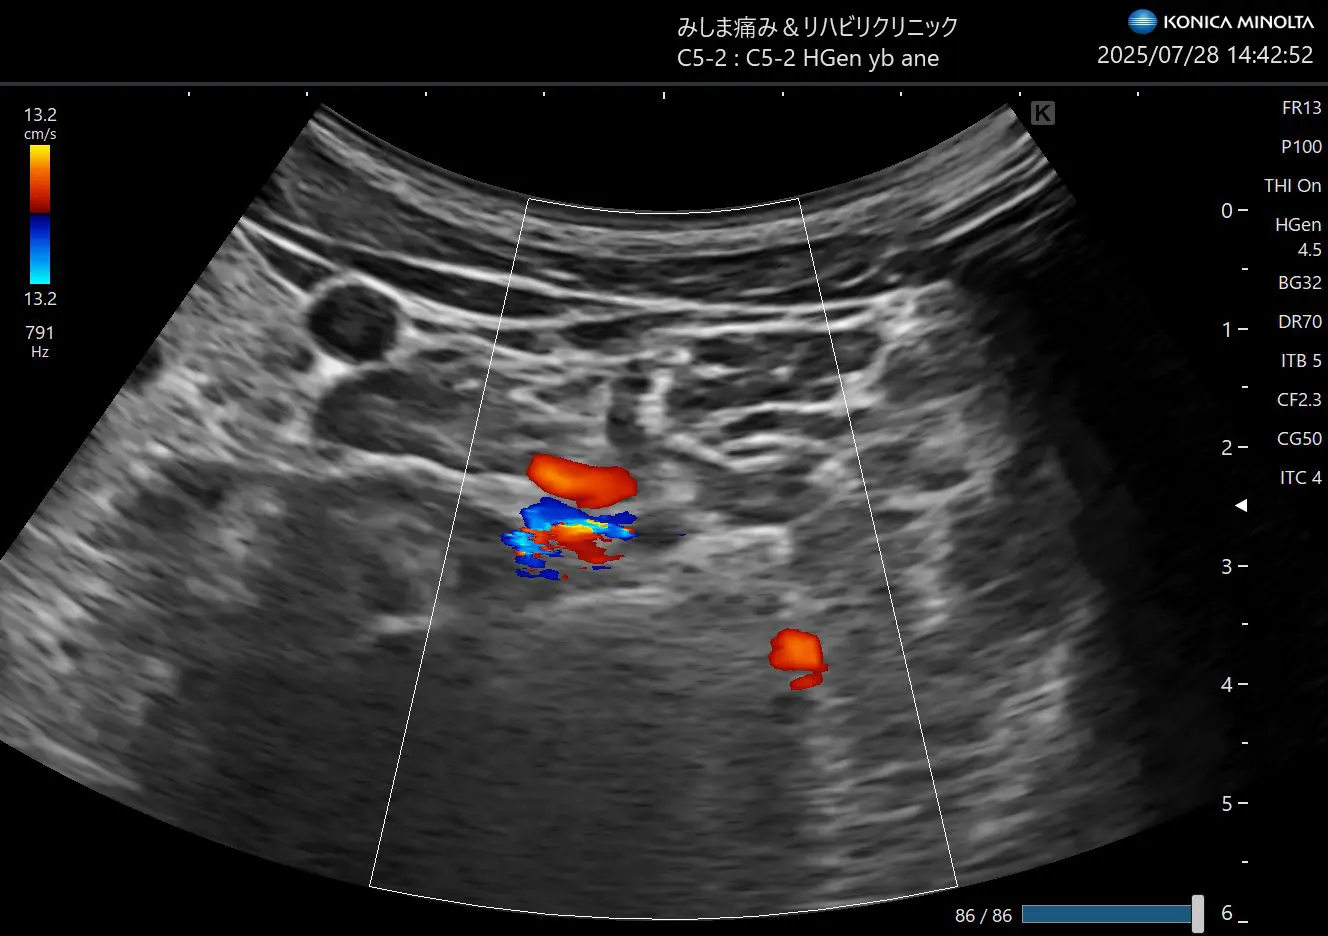

そこで、今回発表された方法は前方アプローチ系椎間孔アプローチです

この方法では、朴先生曰く神経根だけの描出にとどまらず、脊柱管内の造影までされたということでとても効果的な方法である可能性が高いです。

朴法はこのレベルから少し頭側にエコープローブを移動します。そうすることで後結節という骨が消えて前面に椎骨動脈、後面(背側)に神経根というビューとなります。

ではこれをエコーでしてみるとどうなるかということですが、なかなか難易度が高い

脊髄に入っていく神経根とその隣にある椎骨動脈を確認します。

ただ、針を持っていくのは少し熟練が必要です。